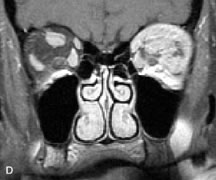

Lymphomas have MRI characteristics similar to those of inflammatory lesions in that they are hypointense to fat and isointense to muscle on T1-weighted images (Fig. 22). They may appear hyperintense to fat on T2-weighted images, perhaps owing to less fibrosis than that seen in orbital inflammatory pseudotumor, although this is not a consistent finding.31,50,66 Lymphoid tumors typically enhance moderately after contrast injection. Unfortunately, studies have shown that tumor density and homogeneity are similar between inflammatory and malignant orbital infiltrates, and MRI cannot differentiate these lesions.72,73

Fig. 22. A and B. T1- and (C) T2-weighted MR scans demonstrate a poorly defined multicompartmental mass enveloping the lateral rectus, superior rectus, and levator palpebrac superioris muscles. The lesion is isointense to brain on T1- and T2-weighted scans, as is typical for highly cellular neoplasms. D. Postcontrast fat-suppressed T1-weighted scan demonstrates intense enhancement of the infiltrating intraconal and extraconal tumor.